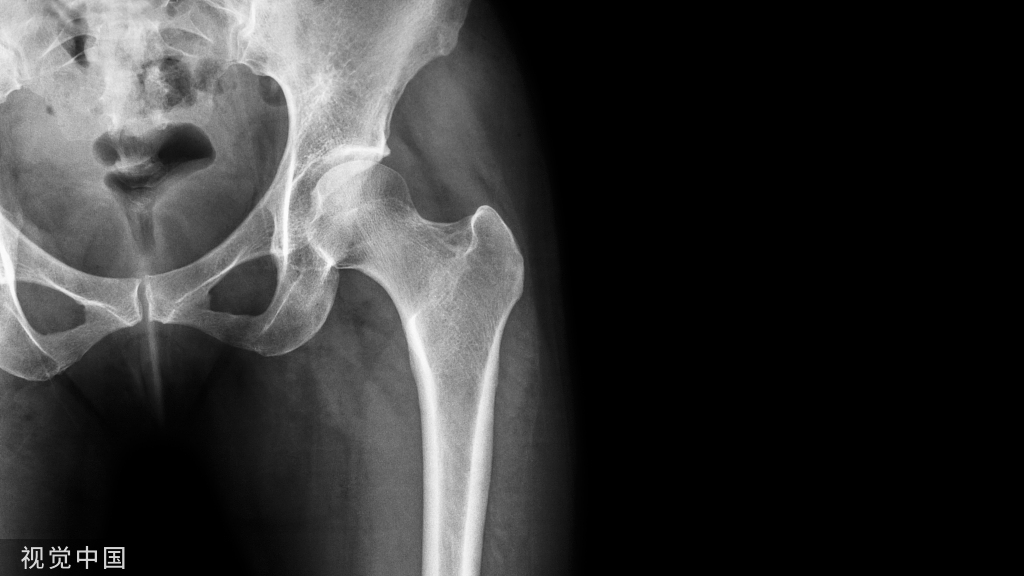

“偷梁换柱”的临床应用在下肢也较为常见。1965年,世界首例人工全股骨置换术用于治疗因佩吉特骨病导致的反复骨折患者。经过半个世纪的发展,人工全股骨置换术作为挽救性手术, 逐渐应用于因肿瘤、骨髓炎或创伤引起的巨大骨缺损的治疗,在保肢重建领域取得了突破进展(图4)

但是,全股骨置换术手术创伤大,手术适应证及术后康复标准仍不统一,而且研究多为个案报道,仍需大样本数据进一步研究。

Wolff定律和骨动态形变定律为骨微观形态的“梁”——骨小梁,赋予了解剖、生理、力学意义,而“偷梁换柱”理论则更多赋予其临床价值。例如,中老年国际骨循环研究协会Ⅲ期股骨头缺血坏死大多局限于负重顶区及其下的压力骨小梁,因此在不干扰周围存活骨组织的前提下精准置换坏死的压力骨小梁和负重顶区是具备临床可行性的, 我们团队正是在该创新理论指导下采用自主研发的部分置换假体治疗中老年ARCOⅢ期股骨头缺血坏死,效果良好(图5)